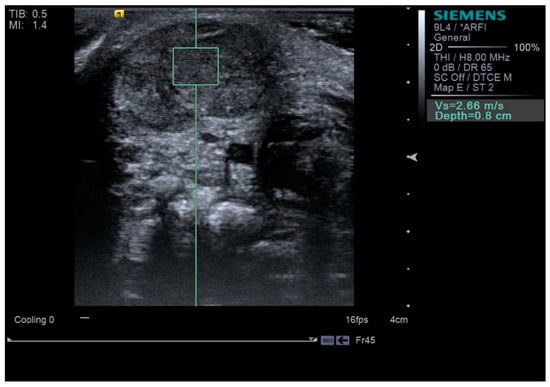

| SWV of SCM (m/s) | Initial | 2.33 ± 0.47 | 1.25 ± 0.27 | <0.001 * |

| After 3 months | 1.56 ± 0.63 | 1.22 ± 0.39 | 0.039 * |

| SWV of SCM (m/s) | 2.33 ± 0.47 | 1.56 ± 0.63 | <0.001 * |